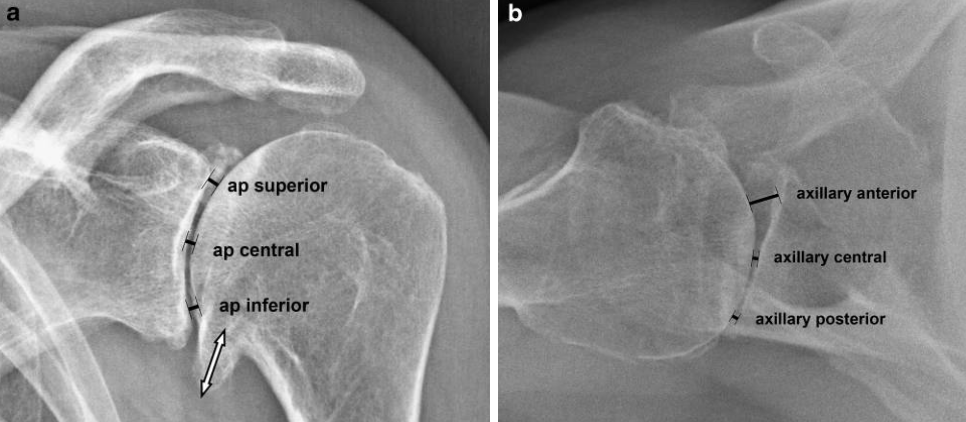

Kicher et al.3 retrospectively examined 120 standardized X-rays of patients with advanced osteoarthritis of the shoulder. They looked at joint space and size of humeral head osteophytes.

As age increased, the joint space narrowed. However, joint space width was not correlated with size of a humeral head osteophyte. It was also not correlated with pain, active or passive range of motion.

(a) True anteroposterior x-ray and (b) axillary view of a left shoulder with advanced osteoarthritis.3